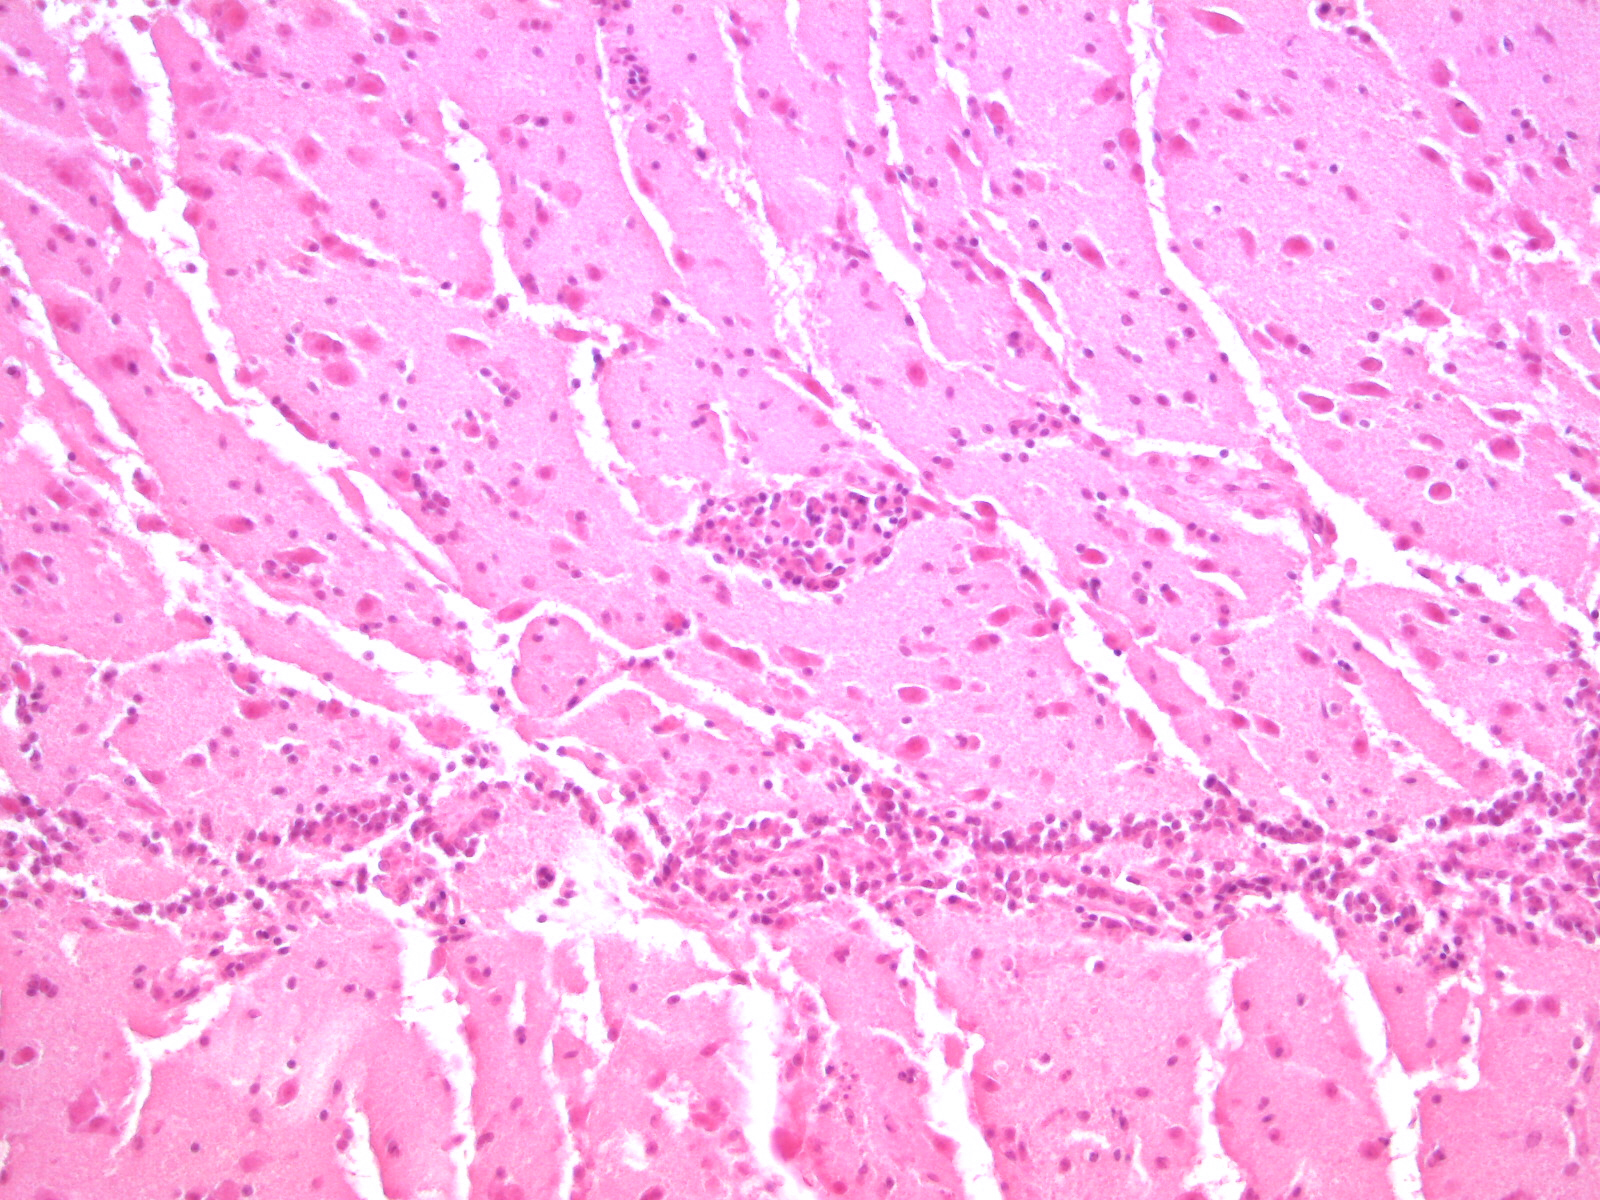

Herkunft und Krankheitsbild

Ursprünglich stammt das Virus aus Afrika und führt vor allem bei Vögeln zu Infektionen. Es ist eng verwandt mit dem West-Nil-Virus, das seit 2018 ebenfalls in Deutschland nachgewiesen wird. Die Übertragung erfolgt durch Stechmücken. Die meisten Vogelarten erkranken nicht. Amseln hingegen scheinen besonders empfänglich zu sein. Die Vögel zeigen zum Teil erhebliche Symptome und sterben in der Folge. Erkrankte Amseln können durch kahles Gefieder, Mattigkeit, Schwanken oder Verdrehen des Kopfes auffallen.

Als Fehlwirt können sich auch Säugetiere, inklusive des Menschen, mit dem Virus infizieren. Infektionen beim Menschen verlaufen meist symptomlos. Selten kommt es zu einer Erkrankung, die sich beispielsweise durch Kopfschmerzen, Fieber oder Hautausschlag äußert. In Deutschland sind bisher keine durch das Usutu-Virus ausgelösten Erkrankungen bekannt.